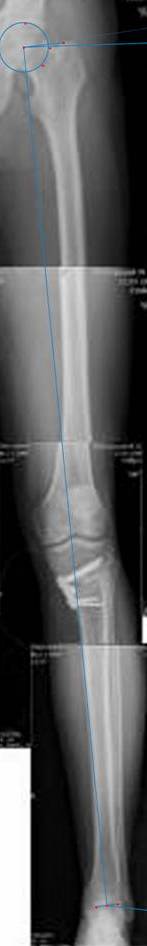

картинки оперированного пациента 40 лет, травма в 2006 году.

оперирован 06.11.2009г - корригирующая остеотомия большеберцовой кости.